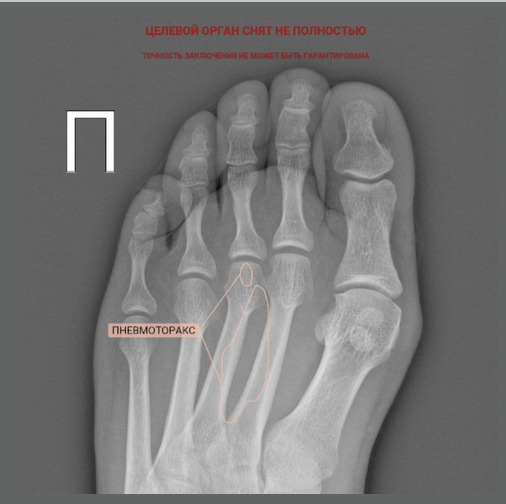

К примеру, неправильно заполненный тег части тела в DICOM-файле и некорректная работа модели по фильтрации снимков может привести к возникновению пневмоторакса в стопе:

Лёгкая поступь